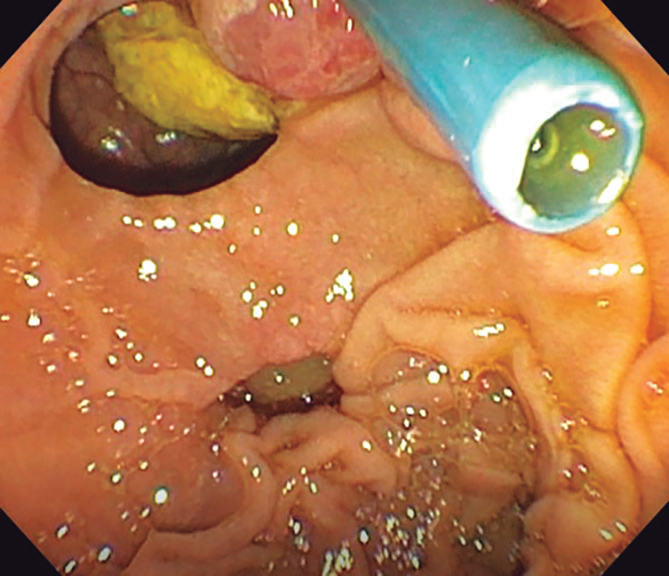

Por la edad del paciente, el hallazgo de los DDP y la dilatación del conducto pancreático principal, se decidió complementar el estudio diagnóstico con la realización de una ultrasonografía endoscópica (USE) biliopancreática, para descartar la presencia de neoplasias pancreatobiliares no evidenciadas en los estudios previos de imágenes. La USE biliopancreática mostró la presencia de un DDP de gran tamaño, dilatación coledociana y escaso barro en la vesícula biliar. El páncreas no presentaba alteraciones y el conducto pancreático principal no se encontraba dilatado. Con los hallazgos descritos, se descartó la presencia de coledocolitiasis y neoplasias pancreatobiliares, y se postuló como hipótesis diagnóstica el síndrome de Lemmel. El tratamiento elegido fue la realización de CPRE más esfinterotomía biliar, dada su baja tasa de morbimortalidad y la alta probabilidad de éxito, sobre la base de los reportes de casos previos. El paciente fue sometido a una nueva CPRE, en la cual se retiró la prótesis biliar (Figuras 4 y 5). La colangiografía mostró dilatación del colédoco (Figura 6), sin evidencia de litiasis. Se realizó el pasaje del balón extractor de vía biliar sin evidenciarse salida de litos ni barro biliar al retirarse este. Posteriormente, se amplió el acceso a la vía biliar mediante esfinterotomía, siendo adecuados el drenaje de bilis y el contraste. El hallazgo de barro en la vesícula biliar fue resuelto mediante colecistectomía laparoscópica. El paciente fue dado de alta sin molestias y el control de la analítica sanguínea fue normal. Tras seis meses de seguimiento, el paciente aún permanece asintomático.